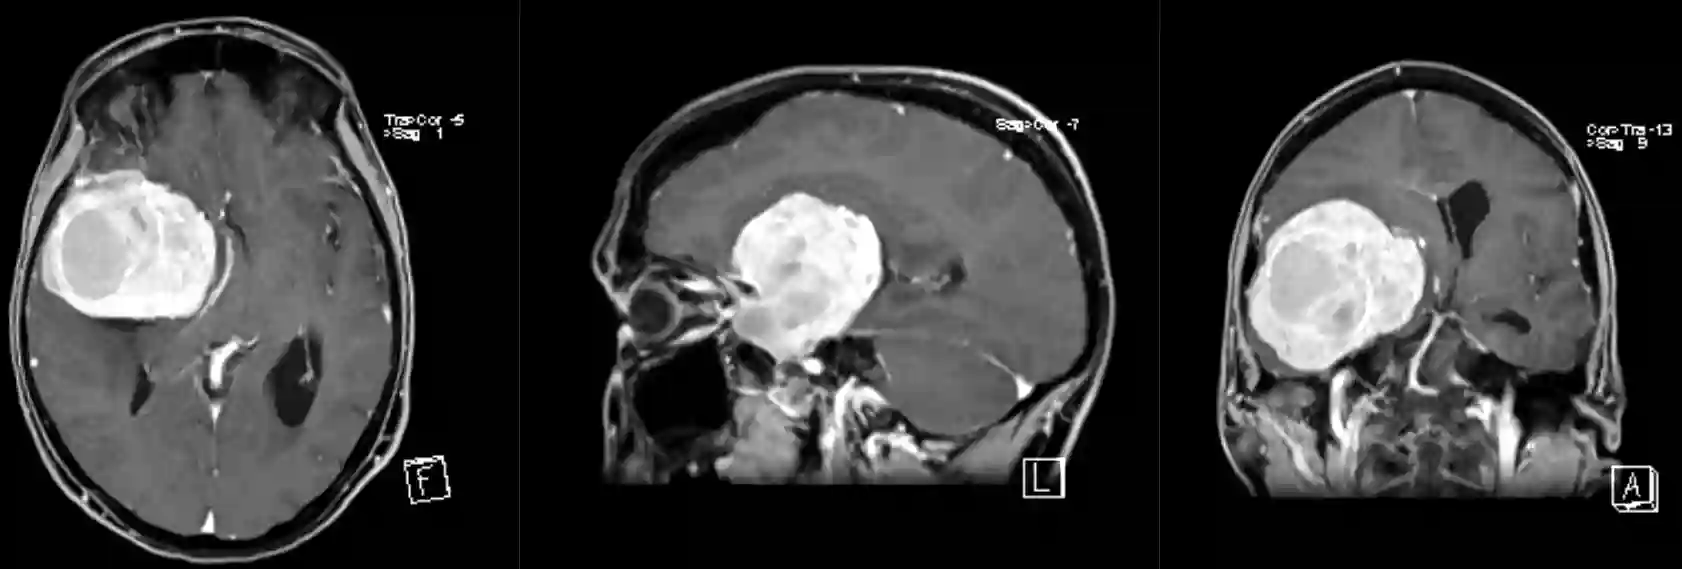

Bildgebung

Der Goldstandard in der Beurteilung von Keilbeinflügelmeningeomen ist die MR-Bildgebung, welche je nach Tumor durch eine CT-Bildgebung zur Beurteilung der ossären Strukturen ergänzt werden kann. In einzelnen Fällen kann eine zerebrale Angiographie indiziert sein, um gegebenenfalls eine präoperative Embolisierung der Gefäßversorgung des Tumors durchzuführen.